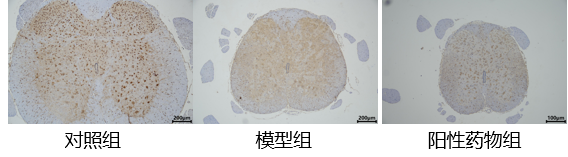

检测指标:给药14天后,进行拉力测试和免疫组化实验,免疫组化用于检测胆碱乙酰转移酶(ChAT)阳性细胞数量。

2.脊髓组织免疫组化

结果提示:对照组ChAT阳性细胞数量平均为39±12个,而模型组平均数为2.6667±3.7个,阳性药物组数量则为26.5±0.7个;且模型组健侧同样出现了ChAT阳性细胞数量降低的情况,平均为3.666±4.7个;这说明腰椎腹侧神经根牵拉导致了L3-L6段脊髓损伤,神经传导受损,并且模型组有扩大到对侧的现象。